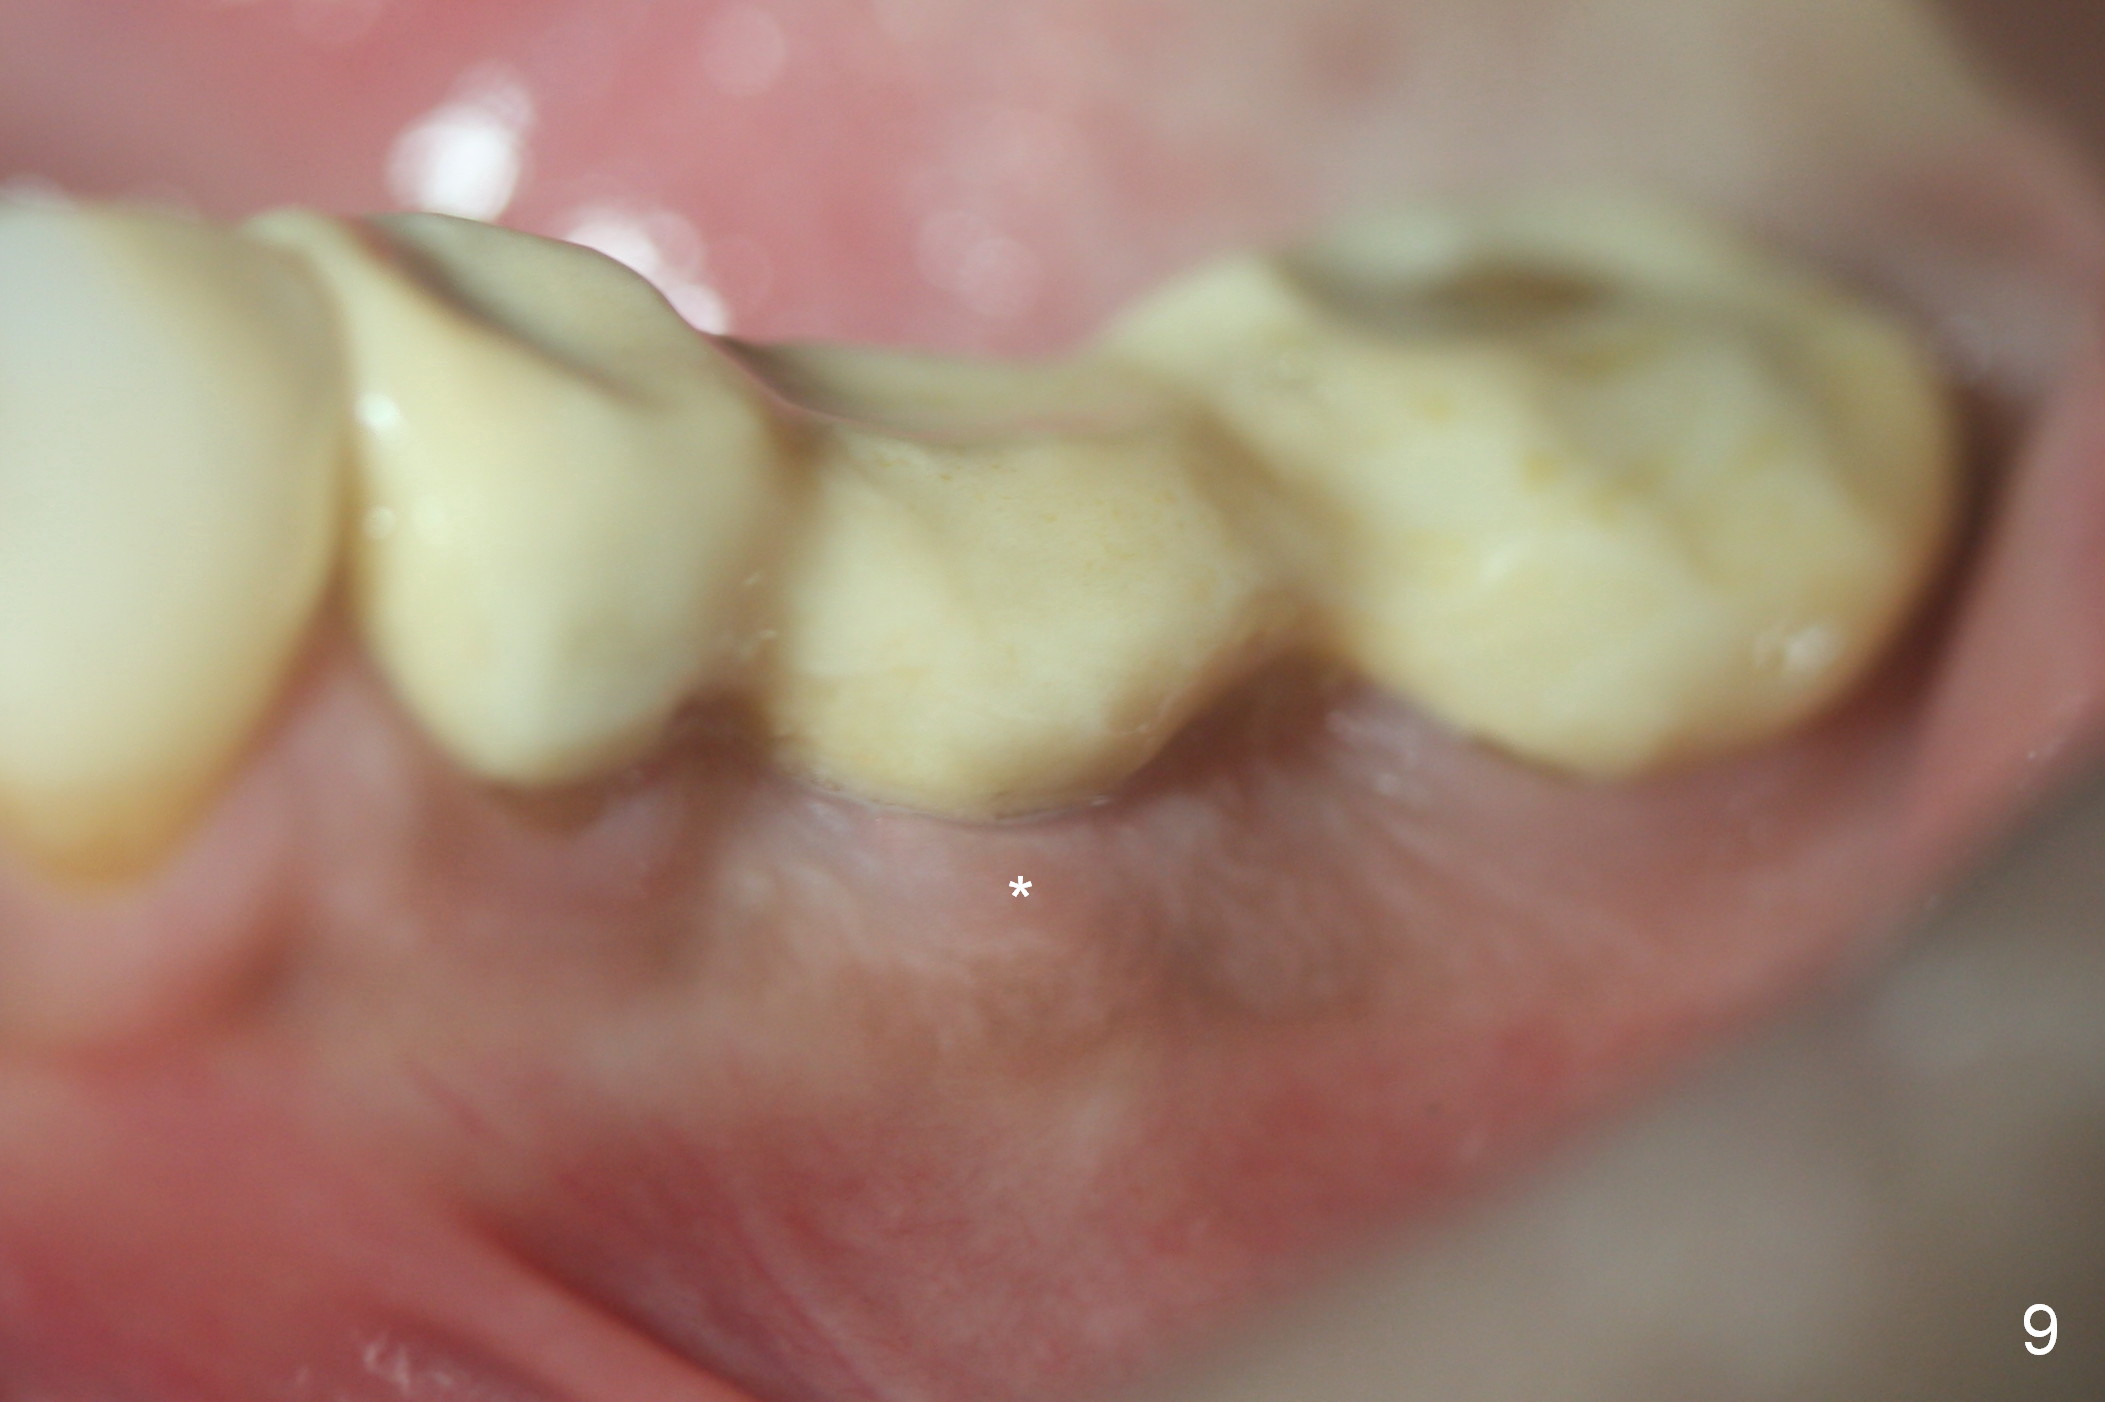

The patient returns for restoration 13 months postop with implant osteointegration (Fig.8) and formation of gingival cuff around the implant/abutment (Fig.9 *). In fact the immediate provisional seems to help mastication to certain degree (Fig.10). Probably it has resisted supraeruption of the opposing dentition. Impression is taken without torque of abutment screw. He smokes again.